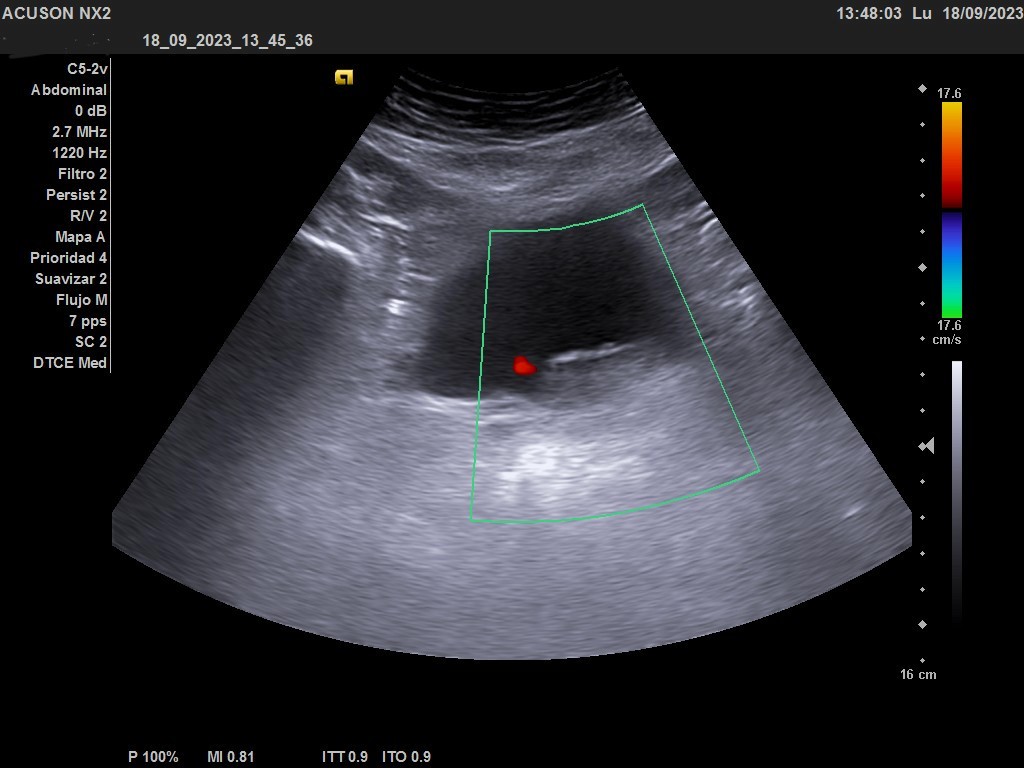

Hallazgos ecográficos

Ecografía clínica urológica: vejiga moderadamente replecionada. Se visualiza en pared posterior imagen hiperecogénica que no capta al Doppler color, de características sospechosas de malignidad. Riñones sin alteraciones en parénquima ni signos de hidronefrosis.